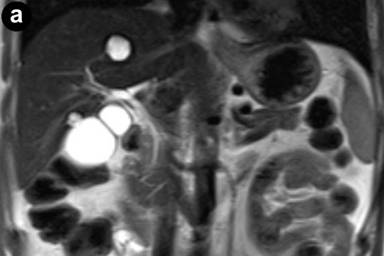

MR imaging was successively performed to evaluate and characterize the nature of the biliary stenosis by acquiring axial and coronal T1- and T2-weighted with/without fat saturation images integrated with MRCP T2-weighted hydro-cholangiographic sequences. In particular, the patient received 900 mL of superparamagnetic oral contrast material (Lumirem®, Guerbet, Paris, France) 20 min before the study. Post-contrast acquisition was performed after the intravenous administration of gadolinium diethylenetriamine pentaacetic acid (DTPA) in a volume of 20 mL with 2 mL/s acquiring T1 fast-field echo short-time inversion recovery (FFE-STIR) images. In particular, cross-sectional T1- and T2-weighted and MR cholangiography sequences showed dilatation of the biliary tree including the intrahepatic ducts, primarily of the left hepatic lobe and the common hepatic duct. Furthermore, MR images showed a lengthy stricture with luminal flow-signal preserved, irregular margins as well as abrupt and asymmetric narrowing in the middle third and intra-pancreatic segment of the common bile duct (Figure 1). A solid lesion along the common bile duct, at same level of the stricture, appearing as circumferential wall-thickening with a firm component projecting into the duct lumen, was also detected (Figure 2); after the administration of contrast medium, the lesion did not show significant enhancement in the arterial phase; however, late-phase images showed non-homogeneous enhancement (Figure 3). There was no evidence of positive lymph nodes or metastatic disease; the characteristics of the MR images were suggestive of a malignant primary stenosis probably by extra-hepatic cholangiocarcinoma. Furthermore, MR views demonstrated mild enlargement of the pancreas associated with a non-homogeneous signal intensity of the pancreatic tissue due to the presence of a hypointense nodule (Figure 3). A second ERCP examination was subsequently performed, which revealed a stricture immediately above and at the level of the intra-pancreatic common bile duct and the biliary stent was removed; brush cytology did not reveal atypical cells and the final report was not indicative of malignancy.

Figure 1. Conventional turbo spin eco T2-weighted coronal (a.) and cholangiopancreatography (b.) magnetic resonance sequences. MR views show a lengthy stricture with abrupt and asymmetric narrowing in the middle and lower third of the common bile duct; the proximal biliary tree is dilated. |